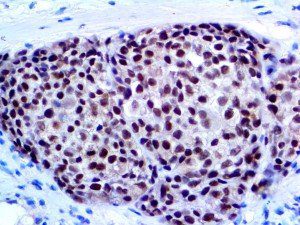

It is the ICU physician who is most likely to witness one of the deadliest manifestations of the abnormal immunological response, the cytokine storm syndrome (CSS). This response is also referred to by some as the cytokine release syndrome (CRS). CSS is characterized by continuous activation and expansion of macrophage and lymphocyte populations, which secrete large amounts of cytokines, causing the cytokine storm. This massive cytokine release is akin to hemophagocytic lymphohistiocytosis (HLH) disease, a syndrome characterized by initial unchecked and persistent activation of cytotoxic T lymphocytes and NK cells.

Clinical and laboratory manifestations of HLH include fever, enlarged liver and/or spleen, neurologic dysfunction, coagulopathy, liver dysfunction, cytopenias (i.e., low levels of erythrocytes, leukocytes, and/or platelets), hypertriglyceridemia, hyperferritinemia, hemophagocytosis, and eventually diminished NK cell activity as the immune system becomes progressively paralyzed. HLH can be familial (primary HLH) or secondary to another disease process (sHLH), such as rheumatic disease, in which it is referred to as macrophage activation syndrome (MAS, characterized by elevated ferritin).